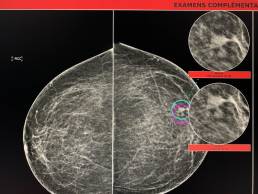

Cas de la semaine (semaine 53, 2020)

Patiente de 54 ans, mammographie de dépistage.

MammoScreen™ pointe un surcroît d’opacité du quadrant inféro-externe du sein gauche.

Un cliché localisé révèle une image a contours spiculée.